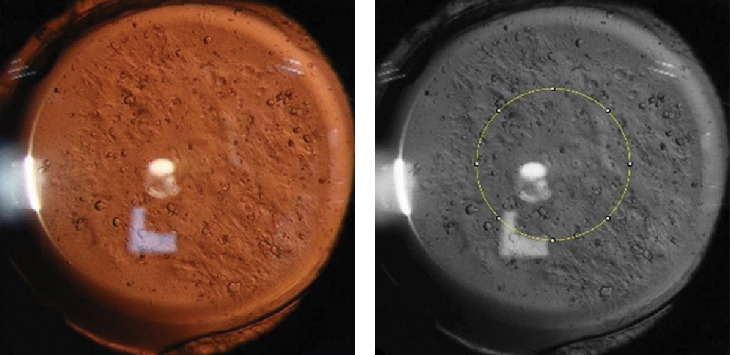

目的:本研究旨在探讨早期后囊膜混浊(PCO)患者高阶像差(HOAs)的视觉质量及特征,为临床评估早期后囊膜混浊(PCO)及Nd:YAG后囊膜切除术的潜在获益提供理论依据。方法:对某三级医院2022年9月至2023年9月诊断为PCO的患者73例(73只眼)进行横断面观察研究。所有受试者均接受验光检查、OQAS和iTrace测量,并在完全散瞳后进行后囊逆行照明摄影。将图像导入ImageJ软件,选择人工晶状体(IOL)直径为3mm的中心区域,记录该区域的平均灰度值(MGV)。统计分析基线数据、首次PCO随访时间、logMAR校正距离视力(CDVA)、MGV、物镜视觉质量参数、失调性晶状体指数(DLI)及各HOAs参数。结果:与对照组相比,PCO组的OSI、MTF截止、SR、三叶膜、Z18、Z24等参数差异均有统计学意义(p < 0.05);而logMAR CDVA、HOs总、彗差、球差差异无统计学意义(p < 0.05)。与MoIOL组相比,MfIOL组PCO随访时间更早,MTF截止时间和SR显著提高,Z7和Z10显著降低(p < 0.05)。基于OSI的亚组分析显示,两组在logMAR CDVA、MTF截止、SR、DLI、HOs total、coma等参数上差异有统计学意义(p < 0.05)。结论:早期PCO对患者客观视觉质量和hoa有显著影响。早期干预可能为植入MfIOL的患者提供更大的视力益处。

Purpose: This study aims to explore the visual quality and characteristics of higher order aberrations (HOAs) in patients with early posterior capsule opacification (PCO), providing a theoretical basis for the clinical assessment of early PCO and the potential benefits of Nd:YAG posterior capsulotomy. Methods: This cross-section observational study included 73 patients (73 eyes) diagnosed as PCO at a tertiary hospital from September 2022 to September 2023. All subjects underwent optometric examinations, OQAS, and iTrace measurements, followed by posterior capsule retroillumination photography after full mydriasis. Images were imported into ImageJ software, selecting a 3-mm diameter central area of the intraocular lens (IOL), and the mean gray value (MGV) of this area was recorded. Statistical analyses were conducted on baseline data, the first PCO follow-up time, logMAR corrected distance visual acuity (CDVA), MGV, objective visual quality parameters, dysfunctional lens index (DLI), and various HOAs parameters. Results: Compared to the control group, the PCO group exhibited statistically significant differences in parameters such as OSI, MTF cutoff, SR, trefoil, Z18, and Z24 (p < 0.05); however, logMAR CDVA, HOs total, coma, and spherical aberration did not show significant differences (p > 0.05). Compared to the monofocal IOL (MoIOL) group, the multifocal IOL (MfIOL) group had earlier PCO follow-ups, with significantly better MTF cutoff and SR, and significantly lower Z7 and Z10 (p < 0.05). Subgroup analysis based on OSI showed significant differences between the two groups in parameters such as logMAR CDVA, MTF cutoff, SR, DLI, HOs total, and coma (p < 0.05). Conclusions: Early PCO significantly impacts objective visual quality and HOAs in patients. Early intervention may provide greater visual benefits for patients implanted with MfIOL.